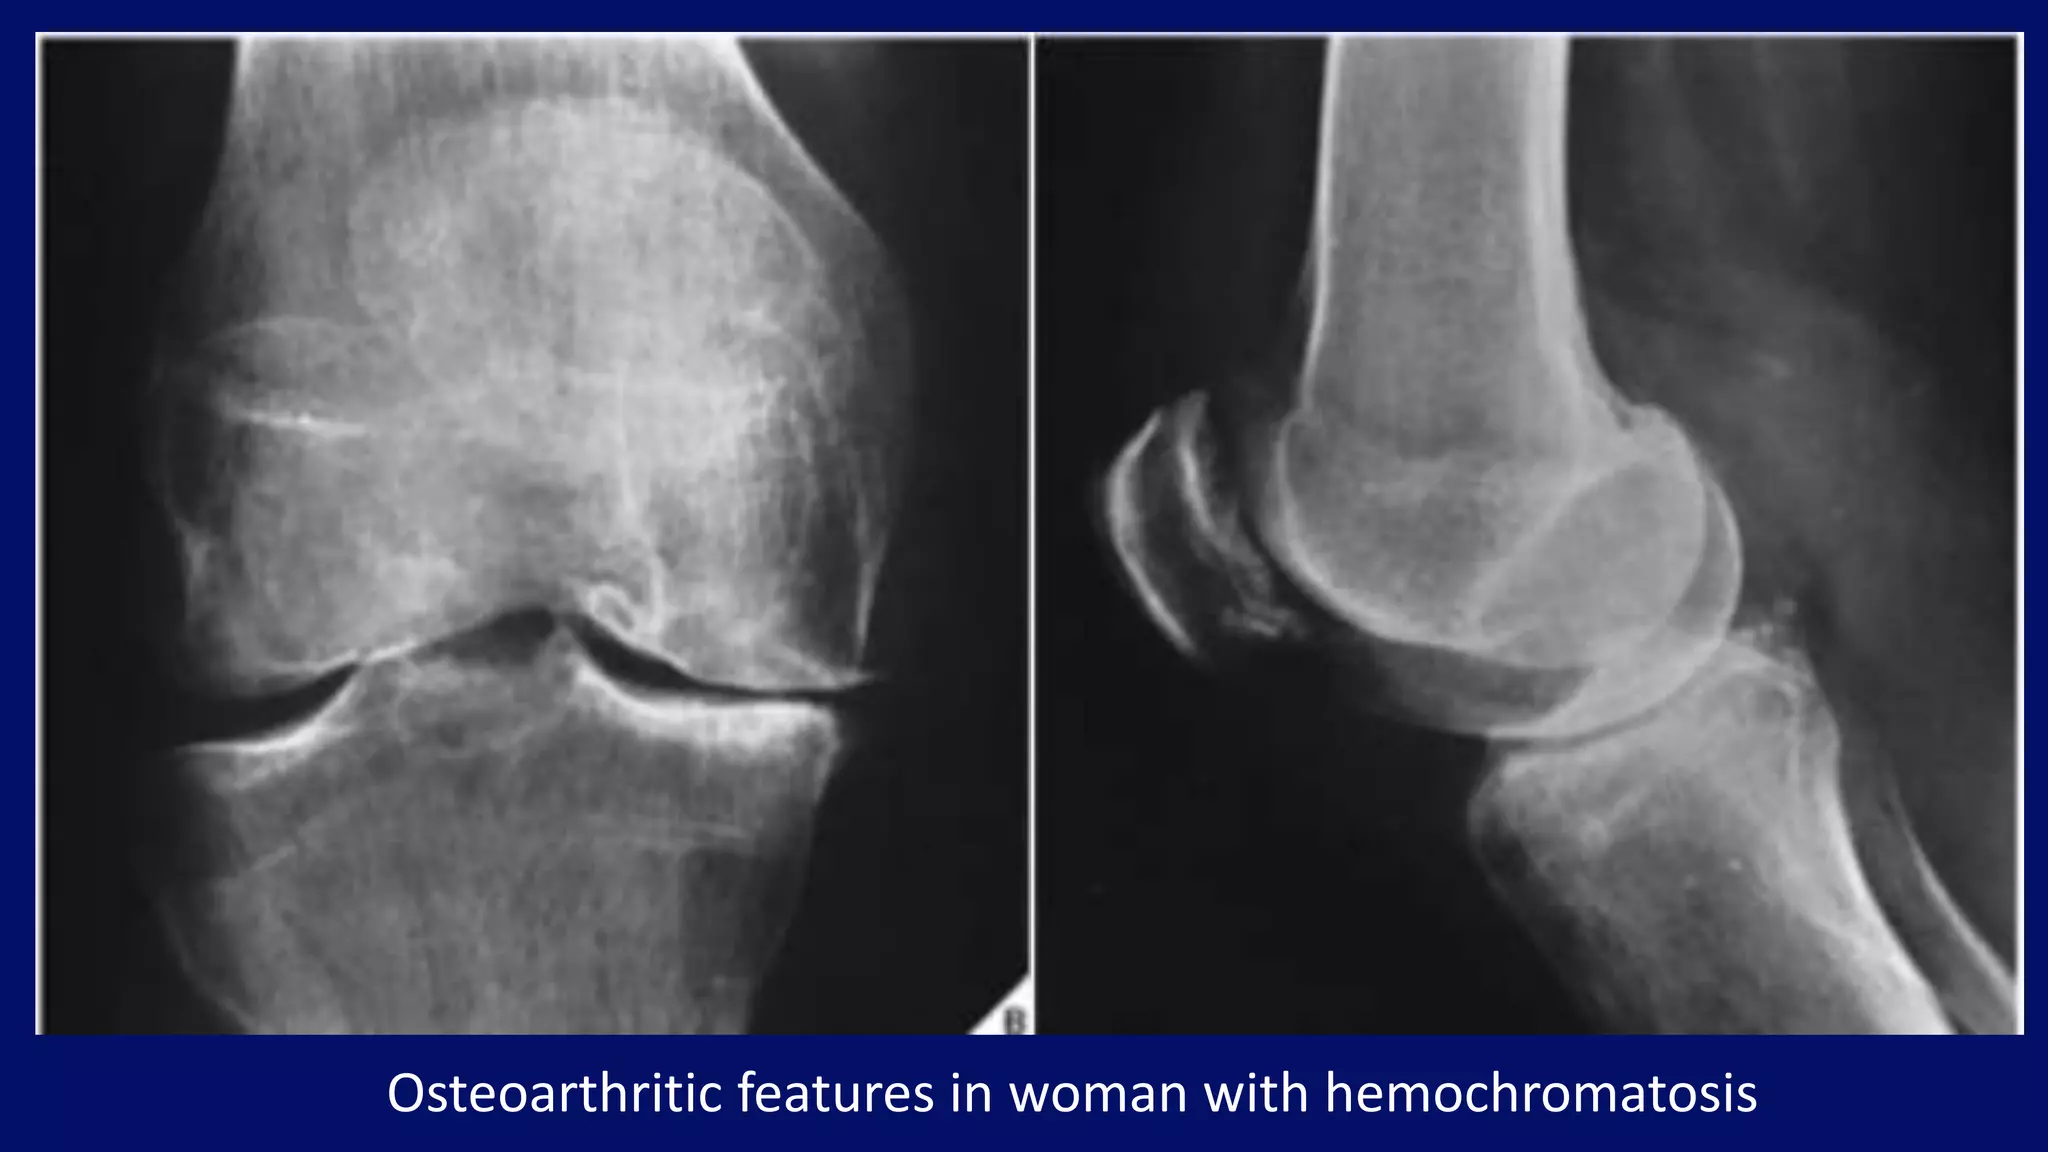

Hemochromatosis

• characterized by iron deposition in various organs

• may be primary (endogenous or idiopathic) or secondary

• affects men 20-times more frequently than women

• 50% of patients with hemochromatosis will have a slowly

progressing arthritis

• features typical of osteoarthritis

• different pattern of joint involvement in hand

• second and third metacarpophalangeal joints

• hook-like osteophytes

• chondrocalcinosis

Radiographic features

Osteoarthritic features in woman with hemochromatosis

• #110 thers is relative sparing of IP joint with invovlment of MCP joints Another typical feature of the disease is the presence of hook-like osteophytes generally seen on the radial aspect of the metacarpal heads. Chondrocalcinosis is seen in association with the metacarpal changes, usually best appreciated in the wrist.

• #111 JSN with subchondral sclerosis with osteophyte formation.